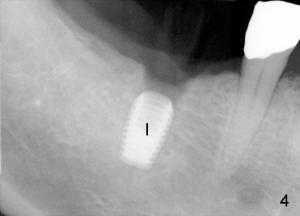

The second precaution to be taken to prevent post-implant infection is to place implant subgingival (submerged with suture to close the incision), instead of supragingival (Fig.3,4). Bicon 5x8 implant is used with bone expansion. The short implant also reduces chance of damage to the inferior alveolar nerve. Paresthesia and hyperethesia (pain) prevents the patient from keeping good oral hygiene post-operatively.

Unfortunately, there is bone resorption around the implant 3 months postop (Fig.6: >, as compared to Fig.4). Granulation tissue is present over the implant (Fig.7 *). The patient complains occasional pain and swelling after implant placement. Bone resorption is confirmed after removal of granulation tissue around the implant (Fig.8 *). After acid etch, Endogain (Fig.9 *, Straumann) is placed around the implant (P: healing plug). Flaps are approximated with 4-0 plain gut suture. Collagen membrane should have been used. Amoxicillin is prescribed, but the patient does not take it. It appears that bone graft to the sockets of #19 helps form an apparently continuous bone plate at the alveolar crest over the mesial (M in Fig.6') and distal (D) sockets, as compared to Fig.4'.

Three months later, the wound heals. X-ray shows that bone loss distal to the implant (Fig.6 double arrowheads) disappears, similar to the one taken another two months later (Fig.10), when the implant is uncovered. The circumferential bone loss shown in Fig.8 is reduced to the distal crest of the implant at the time of uncovering (data not shown).